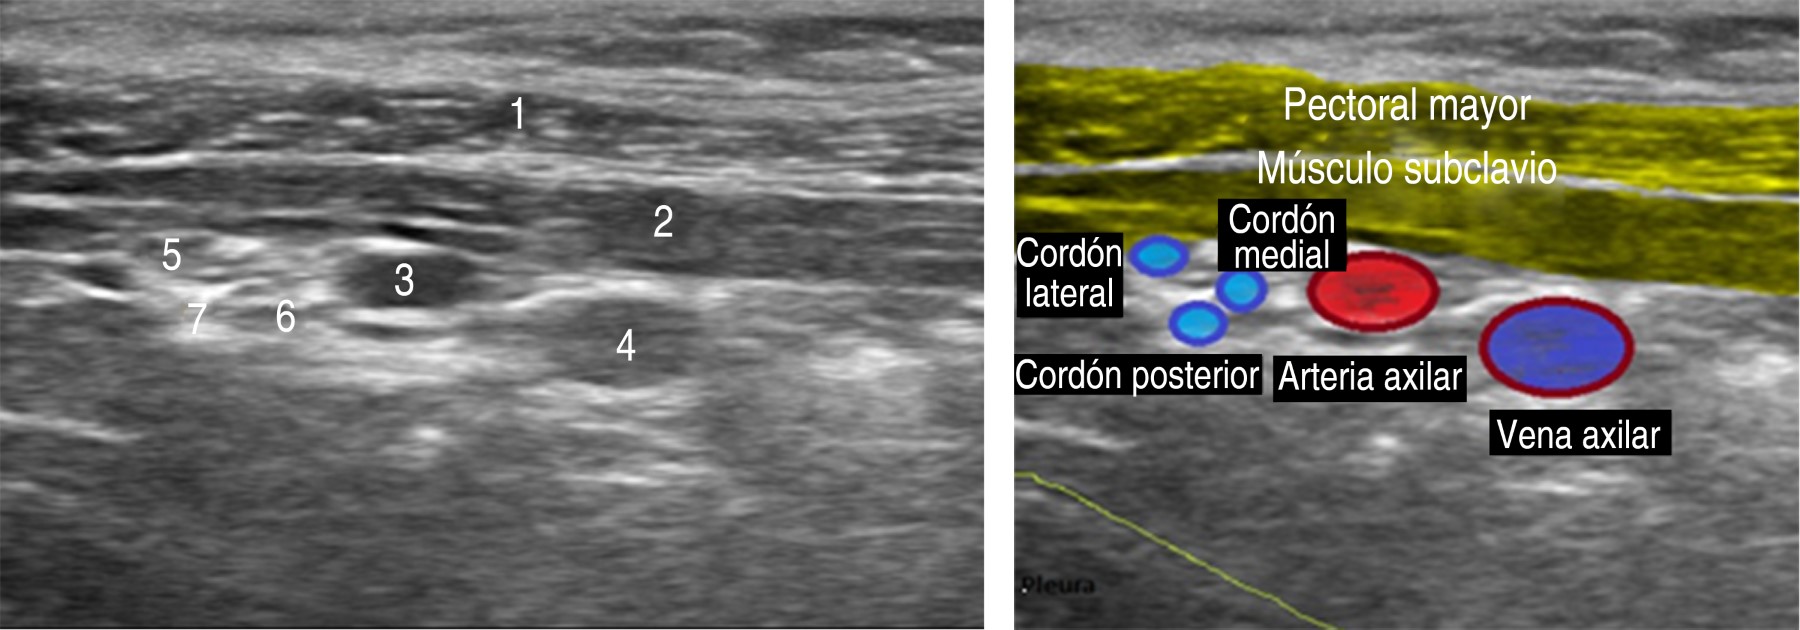

Effectiveness of brachial plexus block with costoclavicular approach and factors modifying sonoanatomy in pediatric patients

Pediatric brachial plexus block has become a good alternative for upper extremity surgical procedures, especially since the advent of ultrasonography. The main aim of the study was to evaluate the effectiveness of the blockade with the costoclavicular approach in the pediatric population, and compare the sonoanatomy of the costoclavicular window with the coracoid one, and determinate if the position of the arm has an impact on the ultrasound image. A total of eight patients with upper limb fractures were evaluated. Of the eight patients, five were male (62.5%), three female (37.5%) with a mean age of 8.8 years. Ultrasonographic screening was performed comparing the sonoanatomy of the costoclavicular and coracoid approaches, better observing the brachial plexus cords and vascular structures with the costoclavicular approach. With the arm abducted 90 and 110o, a better visualization of the neurovascular structures and an improvement in the quality of the block was obtained. The ropivacaine dose was 1.5 mg/kg between 0.3-0.5%, with an average motor block time of 6.7 hours, and an average sensory block of 11.25 hours. There were not complications. In conclusion, the brachial plexus block via the costoclavicular approach in the pediatric population is a safe technique.

Figure 1